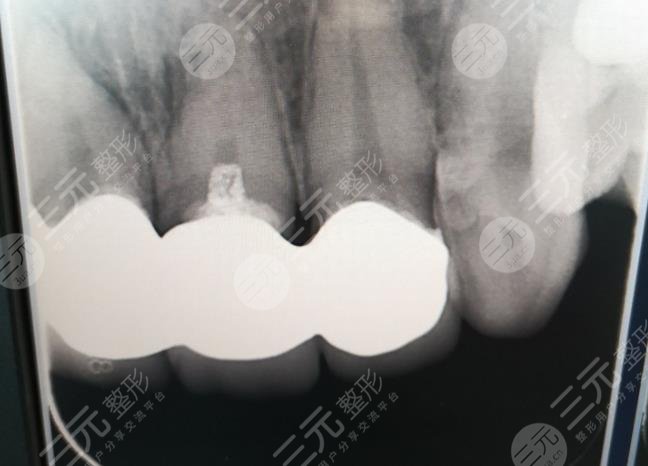

When I went to the hospital for an interview, the doctor asked me to scoop out my teeth on the mold, and a week after that shape, the doctor informed me to go to the hospital for all-ceramic dental plastic surgery, when I first arrived at the hospital, I was actually a little nervous, because I didn't know what would happen, but the doctor and the nurse were very gentle, and explained the whole process to me very carefully, and during the operation, I didn't feel any discomfort, I felt that the whole process was completed in about an hour, and the doctor's technique was very skillful.